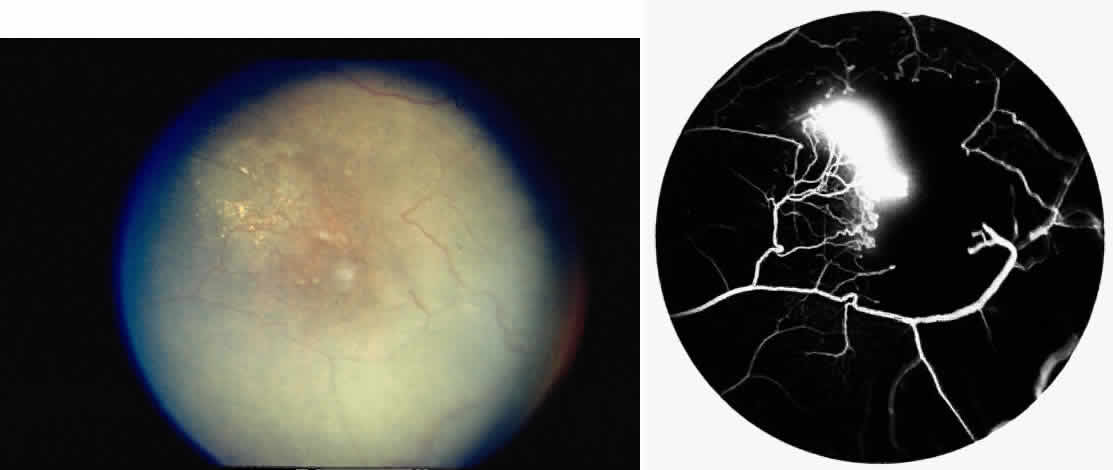

Retinal Hemorrhages, Iridescent Spots, and Black Sunbursts

Retinal hemorrhages (“salmon patches”), found most commonly in the equatorial periphery, can be observed after an abrupt occlusion and rupture of an intermediate-sized retinal arteriole (Fig. 16).113 Because the hemorrhages typically appear adjacent or distal to an intraluminal obstruction, it is likely that ischemic necrosis causes a weakening of the vessel wall and that reperfusion of the vessel causes a rupture of the damaged vessel wall, resulting in a hemorrhage (Fig. 17).100 Acutely, these hemorrhages are bright red, but after several days, the partially degenerated blood acquires a characteristic orange-red color (hence the name salmon patch). In most cases, these hemorrhages are asymptomatic. The majority of these hemorrhages remain confined to the sensory retina; however, blood may leak through the internal limiting membrane into the vitreous or dissect deeper into the subretinal space (Fig. 18).114 Resolution occurs over days to weeks and may result in a focal area of atrophic split retina (a “schisis” cavity), a pigmented retinal scar, or a grayish-white vitreous deposit, depending on the location of the hemorrhage (Color Plate 1B through G).115 The blood is slowly cleared by macrophages.

Intraretinal blood breakdown products, either extracellular or within macrophages, may appear as refractile copper-colored granules (“iridescent spots”") (Color Plate 1H). Macular iridescent schisis lesions have not been described clinically, but they have been observed on histologic examination.114

The occluded vessels may reopen, and the capillary network in the area of a schisis cavity may appear normal; however, more commonly, the vessels will remain closed (Fig. 19). In rare cases, an area of retinal neovascularization may be found within a schisis cavity (Fig. 20).

|

Black pigmented spiculate or stellate chorioretinal lesions (“black sunbursts”) are typically found around or anterior to the equator and adjacent to an arteriole.70 Occasionally, a pigmented lesion may be seen trailing from an arteriole or as a cuff of pigment overlying the vessel (Color Plate 2A).83 Additionally, the overlying arteriole may be occluded. Refractile deposits are often seen interspersed with the pigment. Black sunbursts are believed to be due to deep retinal blood stimulating pigment epithelial migration, hyperplasia, and hypertrophy.116,117 Histopathologic findings support this hypothesis,114 and the development of black sunbursts has been documented in an area of previous intraretinal and subretinal hemorrhage (see Color Plate 1E, F, and G).114,115 An alternative explanation for black sunbursts is the occurrence of choroidal ischemia and aborted choroidal neovascularization.22,118 A spontaneous chorioretinal neovascular membrane was shown to occur within a black sunburst in a 14-year-old girl with homozygous sickle cell anemia.119